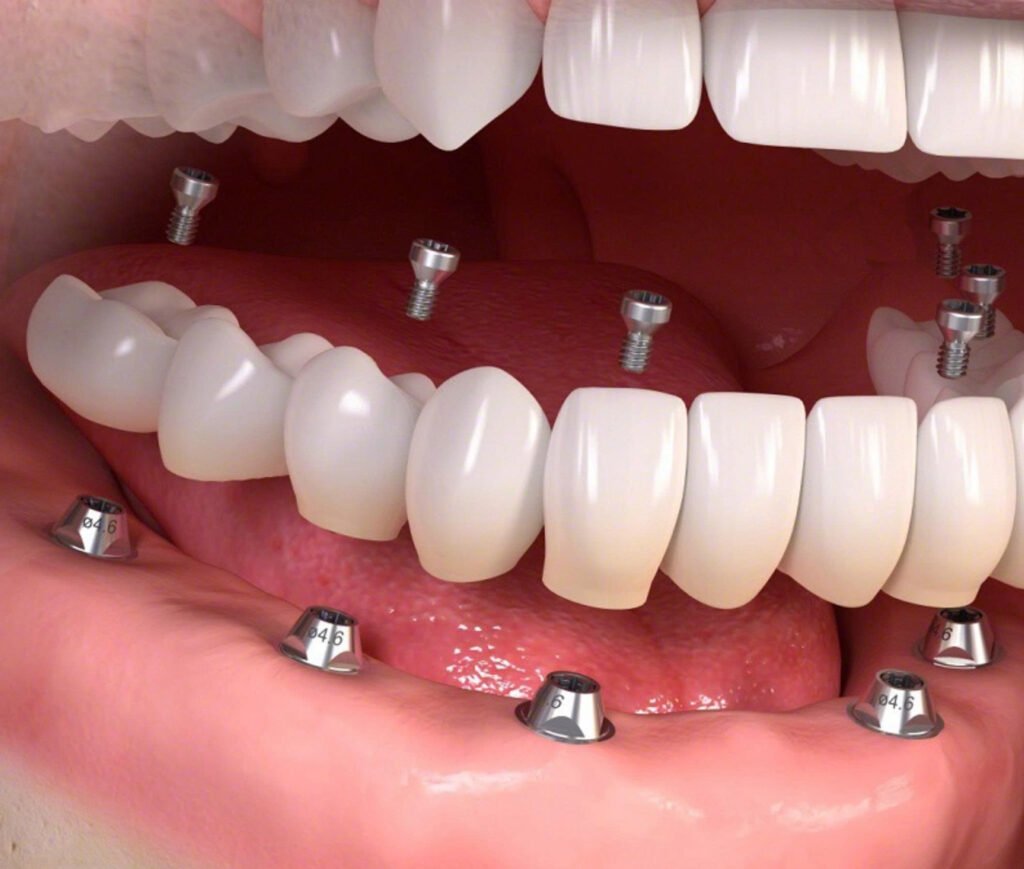

- Dental Implant – Have teeth for chewing after 48 hours